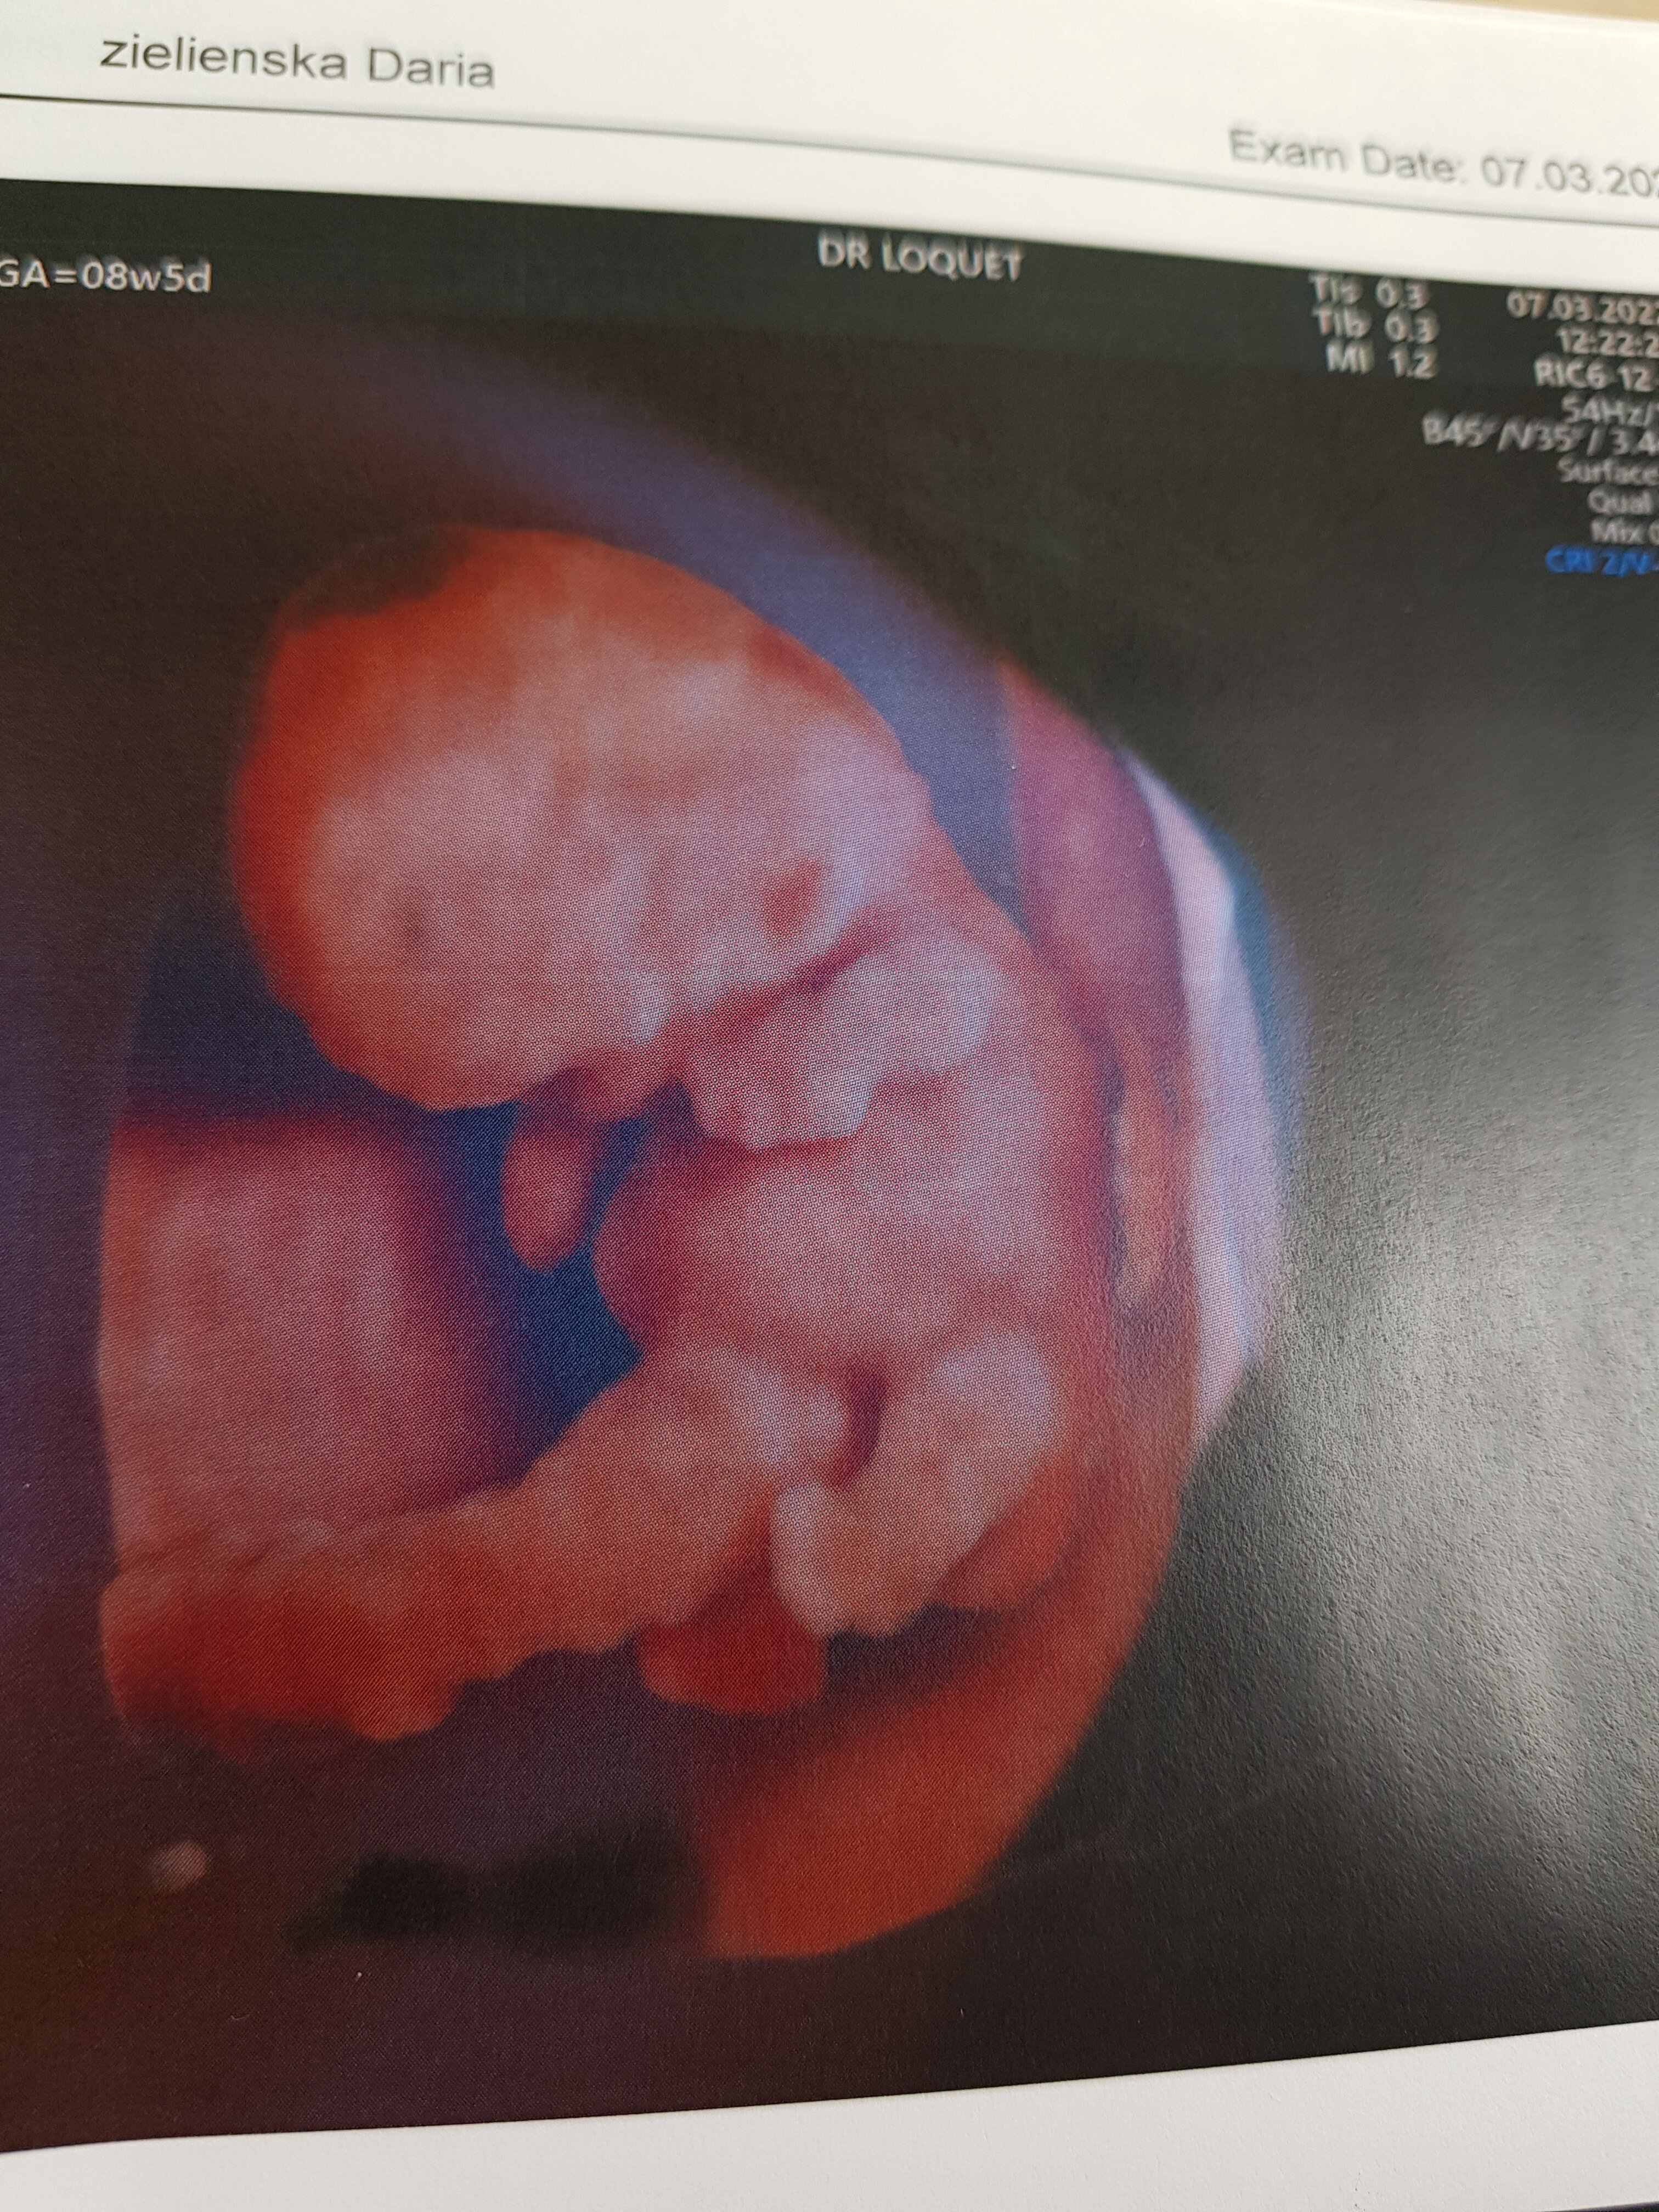

Ciaza zywa, 2,5 cm człowieka 😍

Mam się oszczędzać z racji, że łożysko jest bardzo nisko.

Załączniki

• 20220307_124101.jpg

20220307_124101.jpg

1,2 MB · Wyświetleń: 86